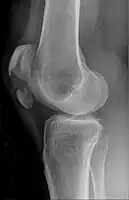

The patella can break in various ways depending on the way it is injured, and into two or more pieces.[1] Types include transverse, with one fracture line and is the most common type,[5] marginal, osteochondral and the rare vertical type, or stellate, where a direct compression force gives rise to a comminuted pattern.[5][7] Patella fractures can be further classified as displaced, where the broken ends of bone do not line up correctly and separate by more than 2mm, or undisplaced and stable where pieces of bone remain in contact with each other.[1][7] If fragments of patella bone stick out from the skin it is known as an open patella fracture, and closed if the overlying skin is intact.[1]

Transverse fracture of patella -